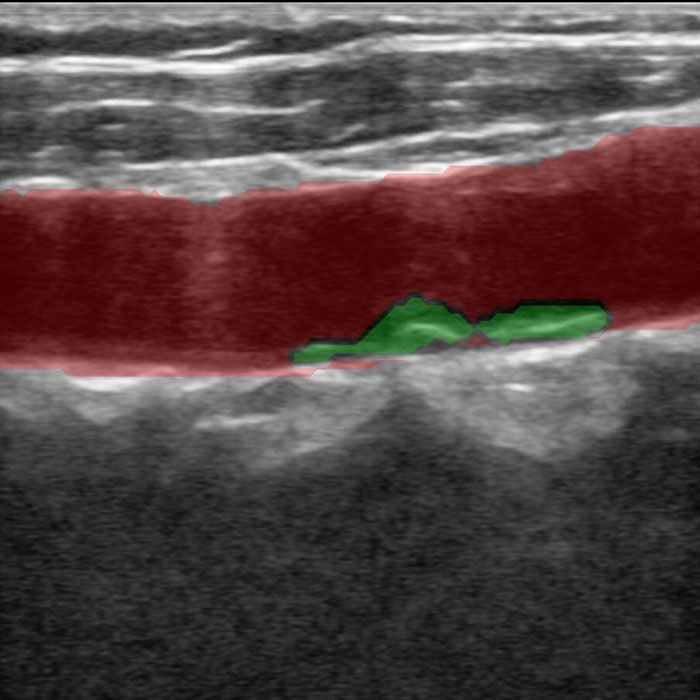

传统超声的多普勒测量非常繁琐,需要设置大量参数手工操作,新名医全球首创一键多普勒测量,AI自动找到血管、自动计算出12项血流动力学参数,让复杂的超声变得像血压计一样,读数就可知道异常,提示粥样动脉硬化、血管狭窄、易损斑块、流速异常等多种脑梗风险。